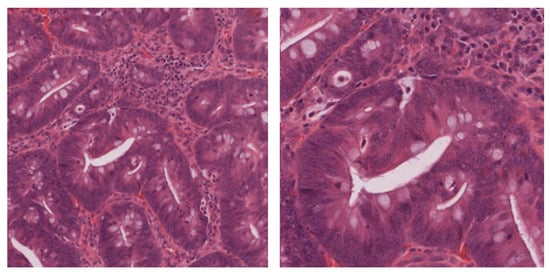

To make the histological images usable by convolutional neural networks, we cropped the WSIs into a large number of small square patches. As the characterization of the colonic polyps depends on both morphological and textural information (respectively, the shape and structure and the cytological characteristics of the glands), the choice of the magnification factor for the cropping may be crucial. More specifically, lower magnifications ensure a better view of tissue architecture, while larger magnifications provide a better characterization of the micro-textural characteristics of the cells (see the two examples in Figure 2). On the other hand, the number of independent patches that can be cropped from the same WSI is proportional to the magnification factor.

Figure 2. Colorectal tissue patches of a tubular adenoma at two different magnifications: 20× (left) and 40× (right).